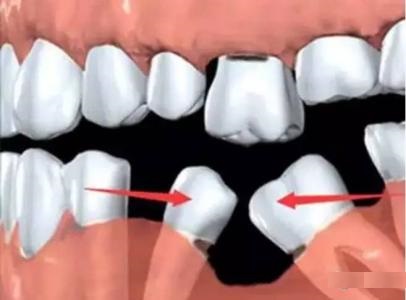

2.邻近牙齿往缺牙区倾倒

由于牙齿倾斜造成清洁不易进而产生牙周破坏。日后治疗恐需利用矫正将牙齿 扶正以后才可以进行假牙制作。